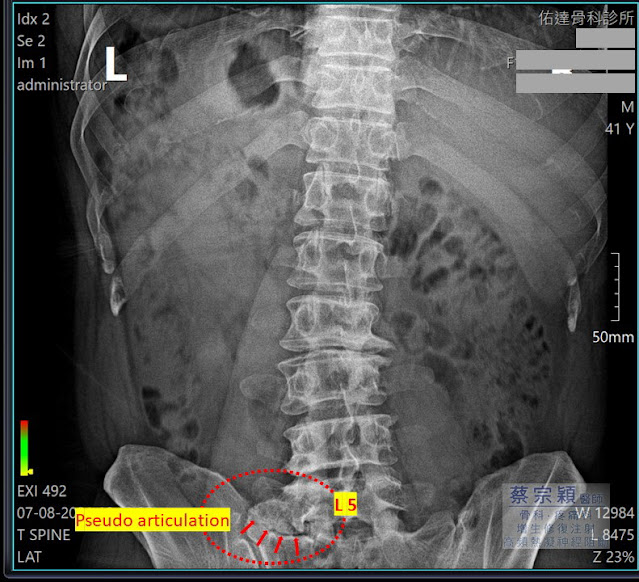

- 如上圖術前 X光顯示,病患第五腰椎左側橫突肥厚增生,與薦椎形成假性關節,以及雙側腰椎小面關節及骨盆的不穩定,同時導致脊椎側彎疼痛。

- (圖 A)顯示正常第五腰椎的橫突,(圖 B)顯示過度增生肥厚的第五腰椎橫突,同時與右側薦椎上端關節化,(圖 C)顯示此不正常的增生形成,與薦椎形成假性關節,合併此關節水腫發炎,同時導致雙側腰椎小面關節的不穩定;以及因肥厚增生的橫突而有神經的壓迫,此即為Bertolotti syndrome。

- Bertolotti syndrome是個先天性的脊椎變異,主要是第五腰椎的橫突變異增生,導致腰椎薦椎變形化(LumboSacral Transition Vertebrae;LSTV),進而導致此增生與薦椎或是髂骨產生假性關節或骨融合,並出現增生硬化等退行性病變。